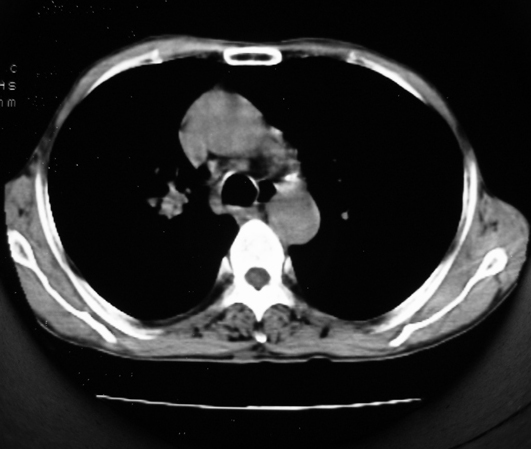

以下是引用同在2007-1-27 14:13:00的发言:[br]支持右侧中央型肺癌伴阻塞性病变.

以下是引用zjzjr在2007-1-27 16:56:00的发言:[br]支持右肺中心型肺癌伴阻塞性肺炎.